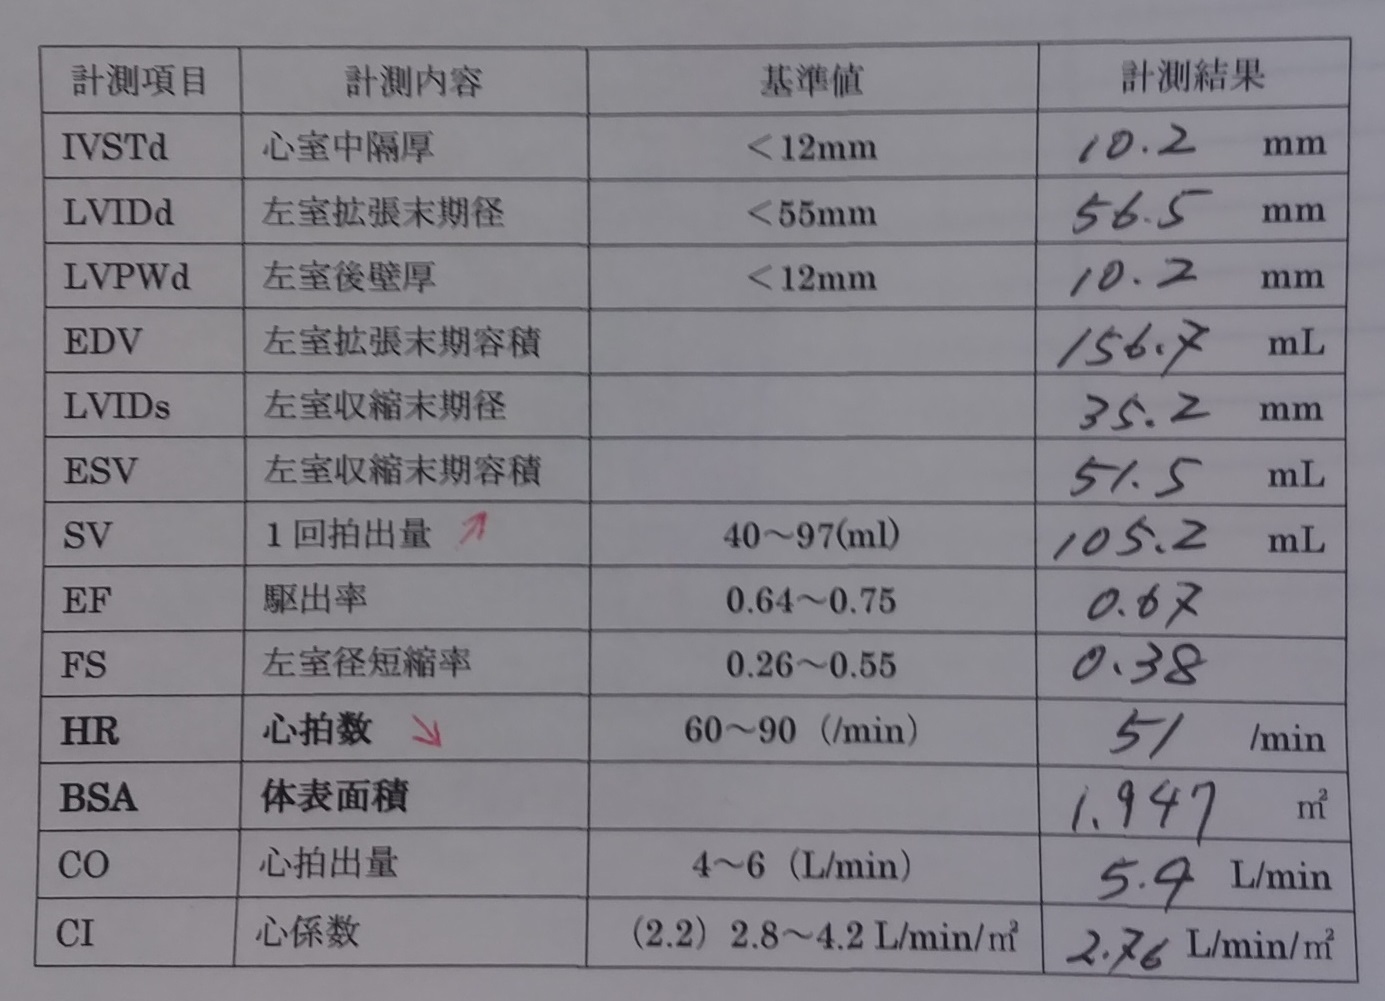

このうち心係数は心臓超音波検査で容易に計測できますが、

実際の現場の臨床では、心係数の確認が重要です。

カテーテル検査が実施できない日常の外来診療においても、

この係数だけで、末梢循環不全の有無を鑑別できることができます。

心係数2.2以であれば末梢循環不全のないⅠ群【死亡率3%】もしくはⅡ群【死亡率9%】、

心係数2.2未満であれば末梢循環不全でⅢ群【死亡率23%】もしくはⅣ群【死亡率51%】です。

M.Yさんの心臓超音波検査で得られた心係数は2.76でした。

2.76>2.2ですから、M.Yさんは末梢循環不全を伴わないⅠ群もしくはⅡ群です。

ただし、Ⅰ群は心機能正常群ですから、明らかな心不全であるM.YさんはⅡ群、

すなわち、末梢循環不全を伴わない肺うっ血タイプの心不全(うっ血性心不全)であることが推定されます。

<心臓超音波>

心臓超音波Bモードによる左心室機能評価

左心室機能計測値

左室径短縮率(%FS)0.38 (基準:0.26~0.55)

駆出率(EF)0.67(基準:0.64~0.75)

左心不全では上記のデータはいずれも低下しますが、M.Yさんのデータはいずれも基準範囲でした。